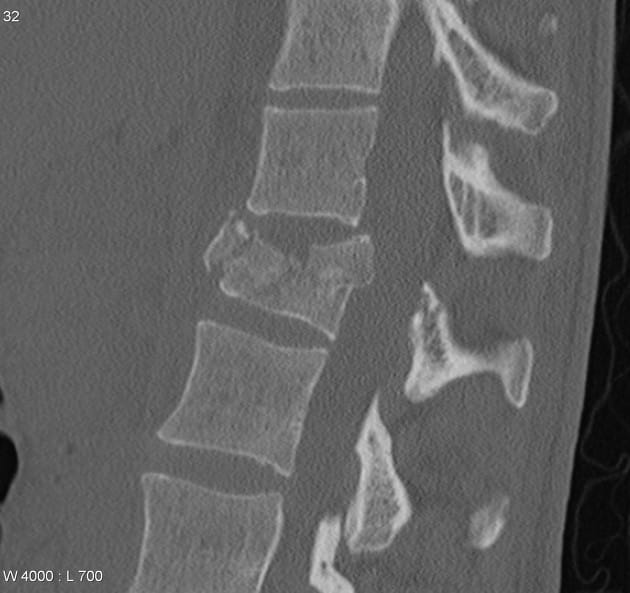

Welcome to my blog! Originally, I had planned for this blog to be about brewing, coding, and data science. Before I managed to write my first substantive post, I had a climbing accident; I forgot to clip in. I fell 12ish feet onto my butt (literally). It sounds a bit comical to write it that way, but it resulted in an L1 burst fracture. I was rushed to the emergency room of the closest hospital, and I had back surgery that evening. I've spent a little more over a month recovering from the accident, with many more months to come. I may go into more of the details of that day in future posts, but here I'm going to focus on things I've learned about spinal injuries.